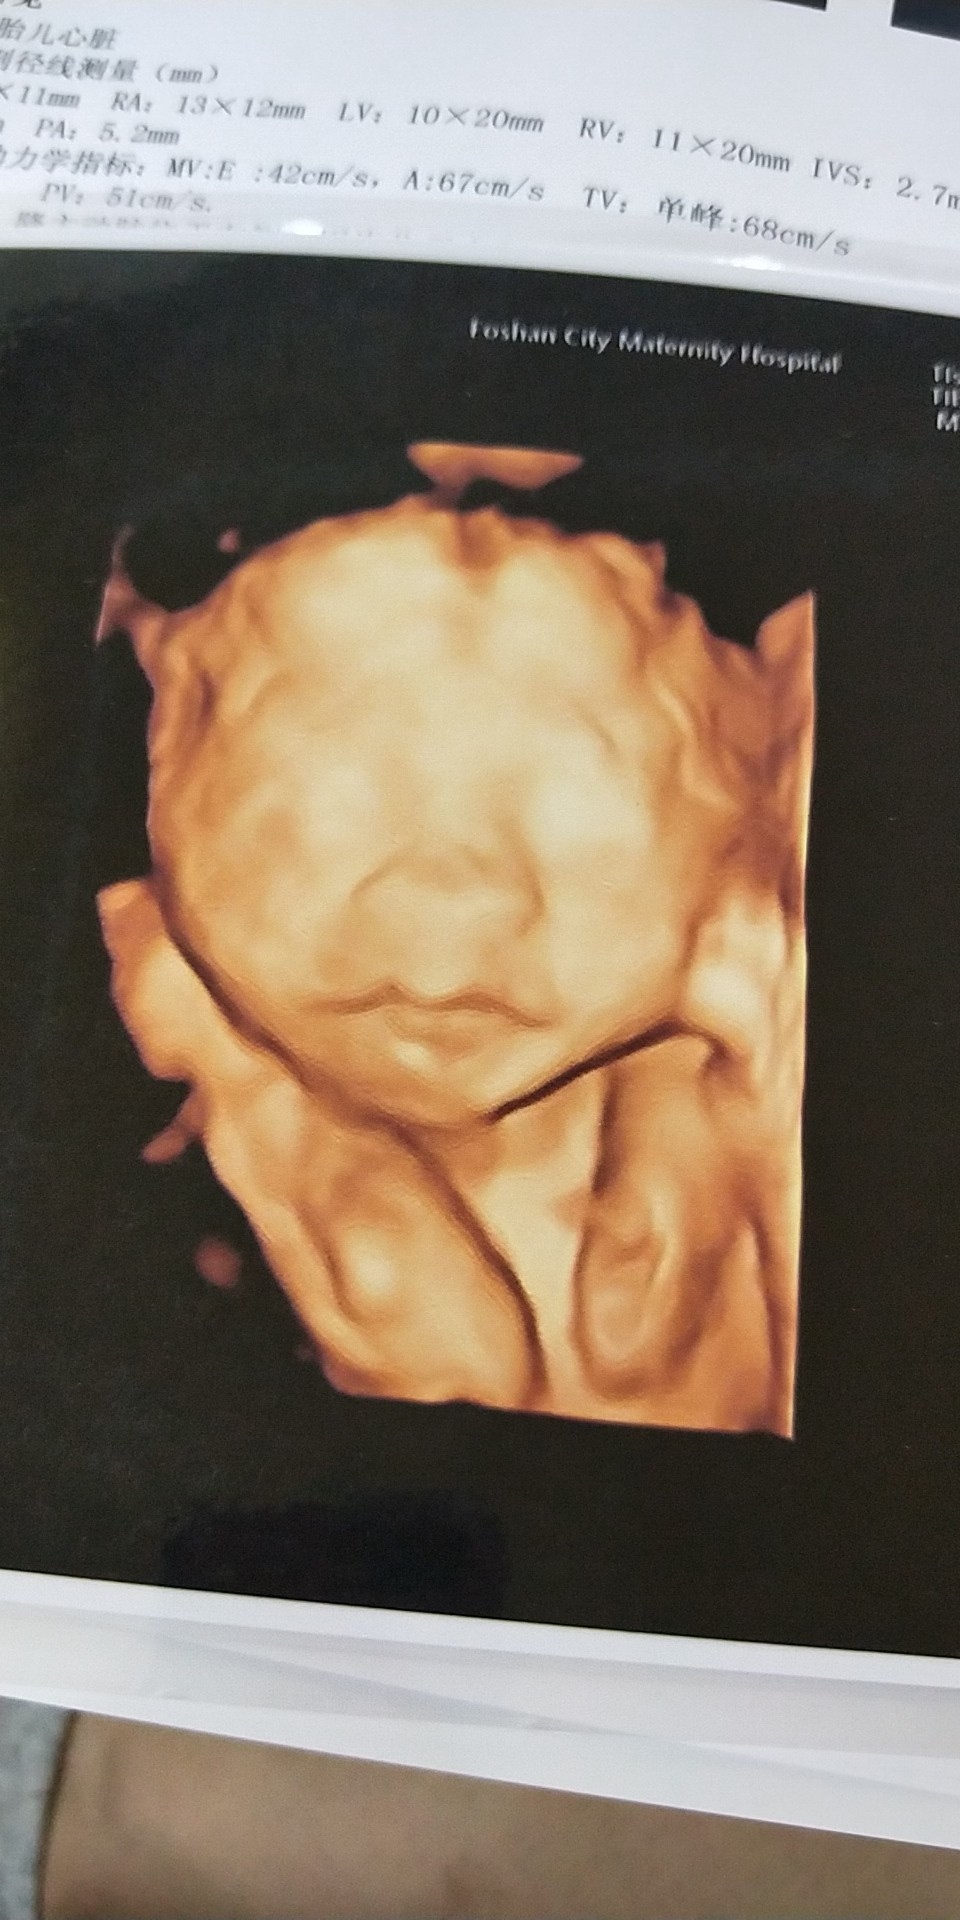

孕24周+4天